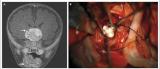

绝对噩梦:盘点那些长错了地方的牙齿

牙齿的整洁,甚至关系到社交活动和地位。但是你是否知道,牙齿不仅仅长在口腔内的牙床上,还有可能长在不应该生长的地方,甚至是在肿瘤内?本文介绍了几个在非口腔的其他位置发现牙齿的医学奇闻。

牙齿

畸胎瘤

肿瘤